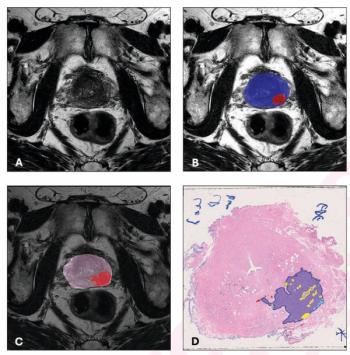

A deep learning multimodal model that incorporates MRI features offered nearly double the sensitivity for predicting post-prostatectomy biochemical recurrence of prostate cancer in comparison to the traditional CAPRA-S scoring system.

The use of adjunctive bpMRI-based AI led to 10 percent and greater increases in lesion-level PPV for csPCa and PCa with a threshold of PI-RADS > 3.